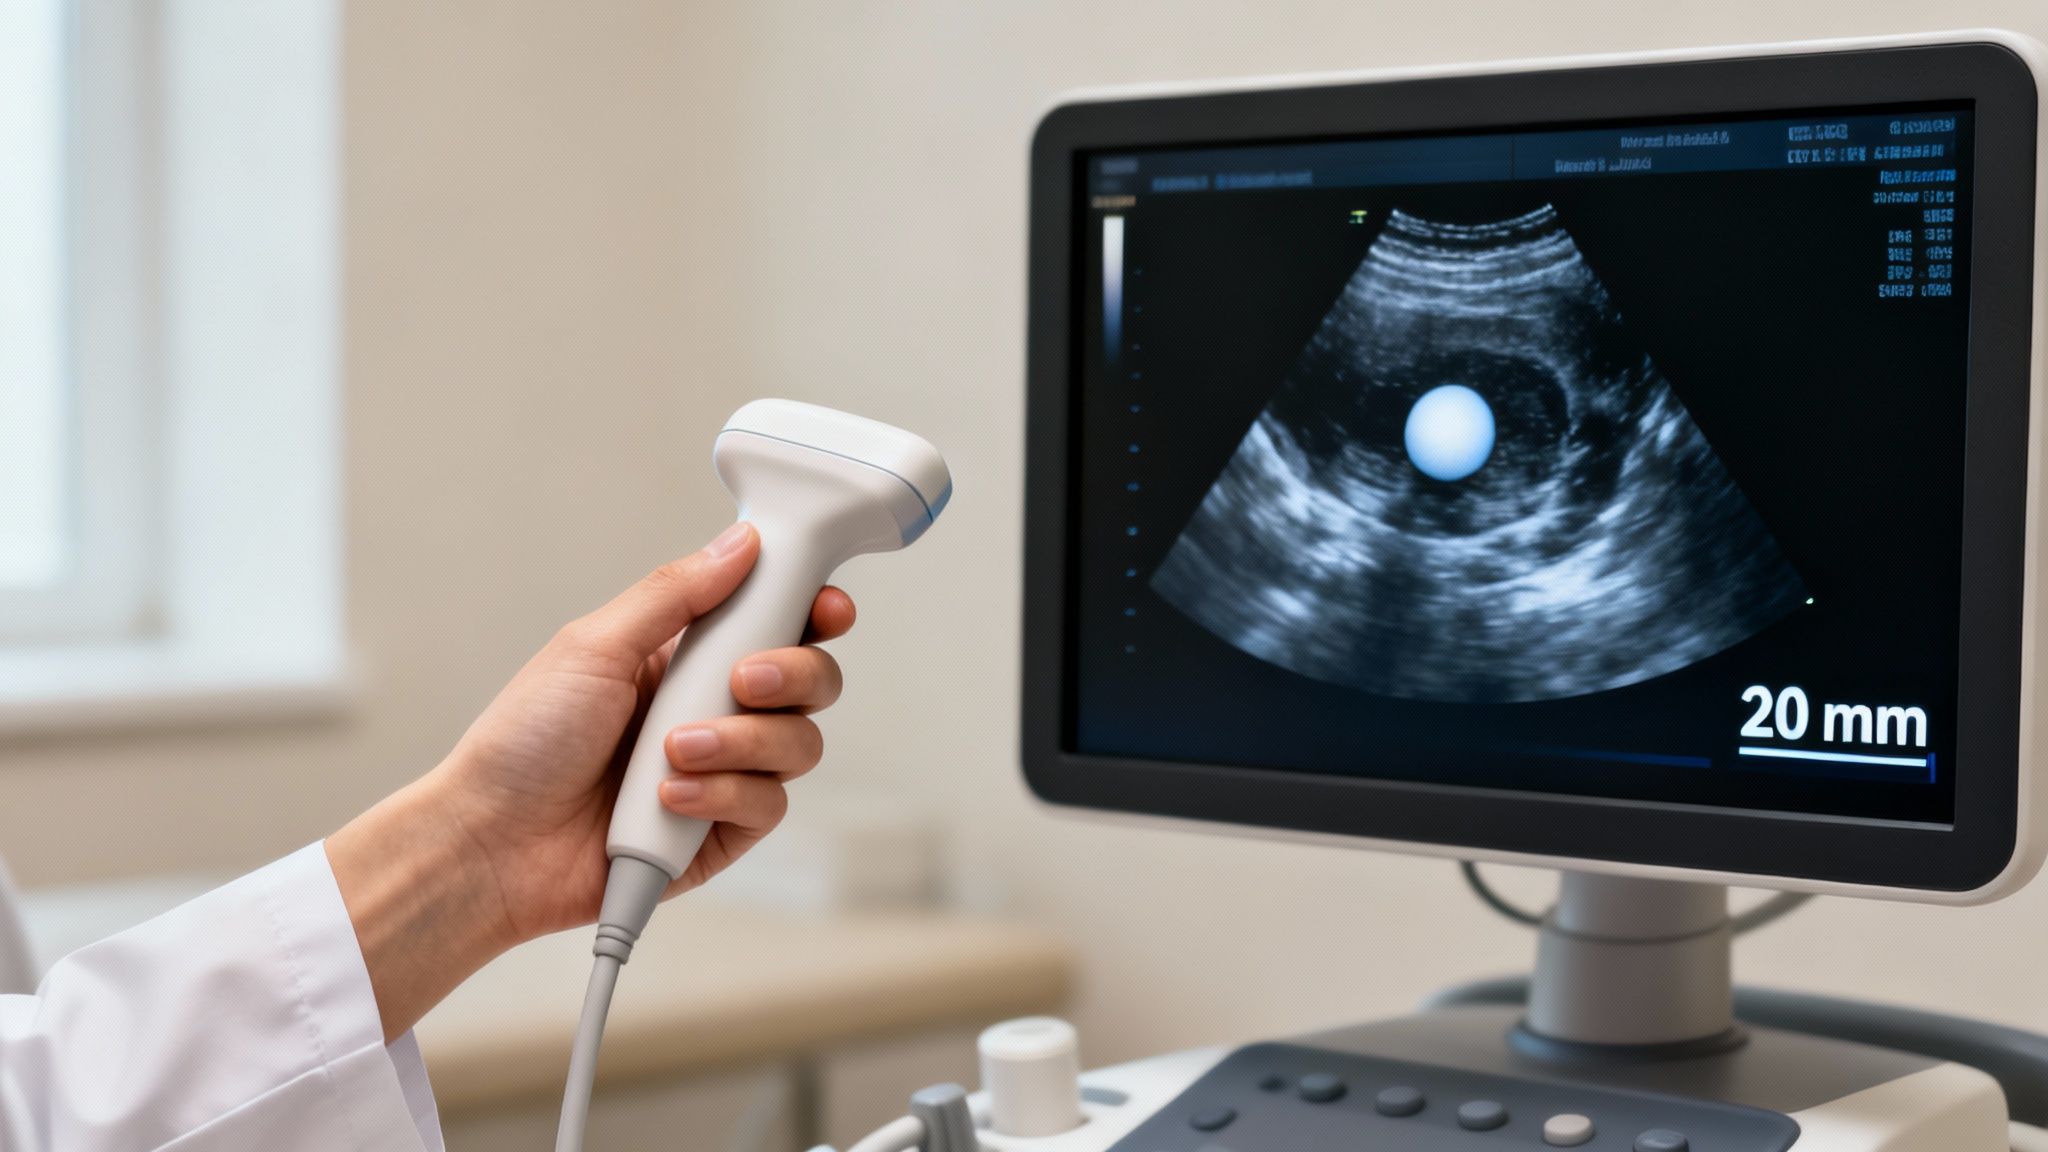

How Doctors Track and Measure Follicle Development

When you're trying to conceive, timing is everything. But how do doctors figure out the perfect moment? They don't just guess. Instead, they use a highly precise process called follicular monitoring, which gives them a real-time window into what's happening inside your ovaries. Think of it as getting a personalised, detailed map of your cycle as it unfolds.

The gold standard for this is the transvaginal ultrasound. While the name might sound a bit clinical, it's a simple and painless procedure. By using a small, specialised probe, your fertility specialist gets a close-up, high-resolution view of your ovaries—far clearer than what a standard abdominal ultrasound can provide. This level of detail is crucial for accurately measuring the tiny follicles as they grow.

Typically, your first scan might be scheduled around day 10 to 12 of your menstrual cycle. After that, you'll likely come in every two or three days. This regular check-in allows your doctor to watch the growth rate closely and spot the dominant follicle—the one that’s getting ready to release a mature egg.

During these scans, your doctor is gathering several pieces of the puzzle to see the full picture of your fertility. They aren't just measuring the diameter of the biggest follicle.

Your medical team is also assessing:

The Number of Follicles: Looking at how many follicles are developing gives a good indication of your ovarian response, especially during stimulated cycles.

Growth Rate: A healthy, dominant follicle should be growing at a steady pace of about 1-2 mm per day. Tracking this confirms everything is on the right track.

Endometrial Thickness: The ultrasound also measures the lining of your uterus (the endometrium). For an embryo to implant successfully, this lining needs to be thick and receptive.

By putting all this information together—the follicle’s size, its growth pattern, and the condition of your uterine lining—your doctor can pinpoint your most fertile window with incredible accuracy. This is the key to perfectly timing intercourse, IUI, or the trigger shot for IVF.